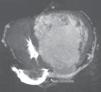

Apresentava em consulta uma pressão arterial de 96‐65mmHg e um sopro sistólico, grau II‐III/VI audível no 4.° espaço intercostal junto ao bordo esquerdo do esterno. O eletrocardiograma (ECG) de 12 derivações mostrava ritmo sinusal, 60bpm e pacing ventricular com sincronia AV mantida. A duração do QRS era de 196ms (Figura 1A). O ecocardiograma transtorácico (ETT) revelava um ventrículo sistémico (VD morfológico) dilatado (63mm) (Figura 2A), com função sistólica global deprimida (≤35% por método de Teicholz [não aplicabilidade do método de Simpson devido à morfologia do VD], relação dP/dt de 379mmHg/s), regurgitação aórtica moderada, regurgitação da válvula AV sistémica (morfologicamente tricúspide) moderada e uma pressão na AP estimada em 40mmHg. Não apresentava dessincronia AV (tempo de enchimento diastólico >40%, com uma boa separação das ondas E e A, sem truncagem da onda A); para a análise da dessincronia interventricular, apenas foi possível a quantificação do período de pré‐ejeção sistémico significativamente prolongado – 161ms (Figura 2B).

Ecocardiograma transtorácico realizado em paciente com transposição congenitamente corrigida das grandes artérias, antes (A, B) e após (C,D) a implantação do sistema de ressincronização cardíaca. Observa‐se uma redução da dimensão diastólica do ventrículo sistémico, de 63mm (A) para 58mm (C) – marcador de possível remodelagem reversa, bem como o desaparecimento do atraso eletromecânico sistémico quantificado pelo período de pré‐ejeção de 161ms (B) para 83ms (D).

Em consulta de seguimento aos seis meses verificou‐se melhoria da classe funcional de IC (classe I‐II da NYHA), redução da dimensão diastólica do ventrículo sistémico (de 63mm para 58mm) (Figura 2C), desaparecimento do atraso eletromecânico sistémico quantificado pelo período de pré‐ejeção (de 163ms para menos de 100ms) (Figura 2D), bem como uma melhoria da fração de ejeção (de ≤35% para cerca de 47% pelo método de Teicholz e melhoria da relação dP/dt de 379mmHg/s para 511mmHg/s).